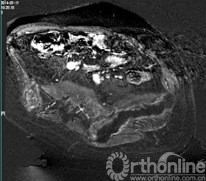

术中实时MR监控及动态测温图像

日前,继在国内率先应用磁共振引导超声聚焦术(MRgFUS)治疗子宫肌瘤后,国内第一例 MRgFUS术治疗转移性骨肿瘤病例在上海市第一人民医院获得成功。首例患者是一位32岁的腺泡样软组织肉瘤髂骨转移患者,该病理类型的肿瘤对放化疗均不敏感。 放射科王悍医生和骨科华莹奇医生对患者进行临床和影像学的综合评估后确认适合该项治疗。骨科沈嘉康医生完善了患者的术前检查和准备工作。麻醉科裘毅敏主任制定了针对性极强的个体化的麻醉方案,由游珊医生和陆文清执行术中麻醉。2014年7月16日,王悍医生和唐纳医生实施了对该患者的无创治疗手术。手术自下午17:30开始,全程约1个半小时,在放射科MRgFUS手术室完成 。术中,王悍医生通过控制聚焦超音波脉冲的激发对转移性骨肿瘤进行消融治疗,经实时温度监测,靶部位的温度达到65~100摄氏度,完全“烧毁”了局部肿瘤组织细胞。 整个过程患者无明显不适,实时心电监护、磁共振影像和体内多点测温的确保了手术的安全性和有效性。术后患者疼痛减轻,返回病房观察一夜后,次日便出院回家,在院之间不到24小时。7月17日,该团队又对另一例肺癌骨转移瘤患者成功实施了无创治疗。

治疗前磁共振图像

治疗后磁共振增强减影图像